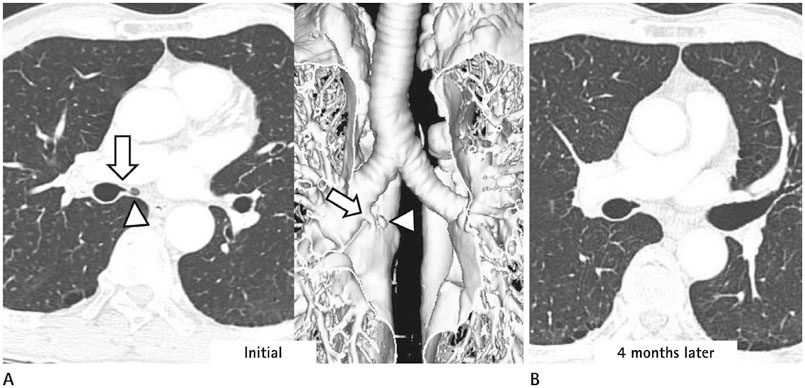

We identified two main types of ACB: blind-end (51.7%) and lobule (48.3%). The blind-end ACB was further classified into three subtypes: blunt (70%), pointy (23.3%) and saccular (6.7%). The lobule ACB was also further classified into three subtypes: complete (46.4%), incomplete (28.6%) and rudimentary (25%). Division location to the upper half bronchus intermedius (79.3%) and medial direction (60.3%) were the most common in all patients. The difference in division direction was statistically significant between the blind-end and lobule types (p = 0.019). Peribronchial soft tissue was found in five cases. One calcification case was identified in the lobule type. During follow-up, ACB had disappeared in two cases of the blind-end type and in one case of the rudimentary subtype.

The proposed classification of ACB based on imaging, and the follow-up CT, helped us to understand the various imaging features of ACB.